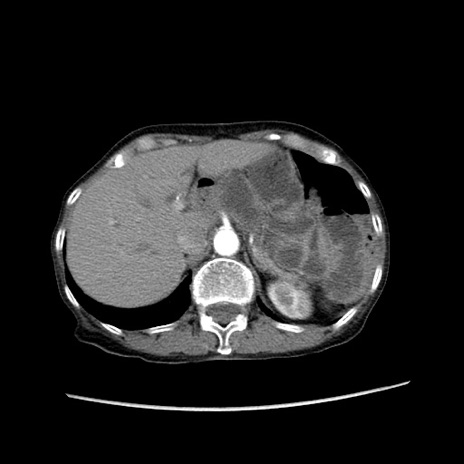

症例25(横断像)

【症例】80歳代女性

【主訴】胸のつかえ感

【現病歴】約9時間前に食後から胸のつかえた感じあり、嘔吐あり、来院。

【既往歴】胃癌(全摘)、胆摘、虫垂炎

【身体所見】心窩部に圧痛あり、反跳痛なし。

【データ】WBC 5700、CRP 0.05